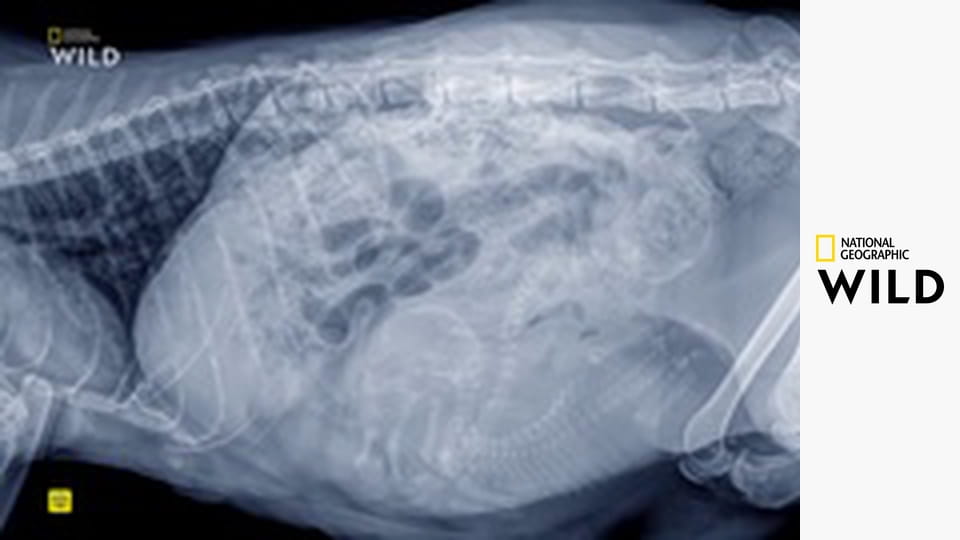

Американское реалити-шоу в котором рассказывается о ветеринаре голландского происхождения Яне Поле, его семье и сотрудниках в его клинике в сельской местности Вайдман, штат Мичиган. Самые различные случаи заболеваний животных, включая коз и поросят, срочные вызовы по скорой помощи, не дают скучать доктору Полу и его коллегам.